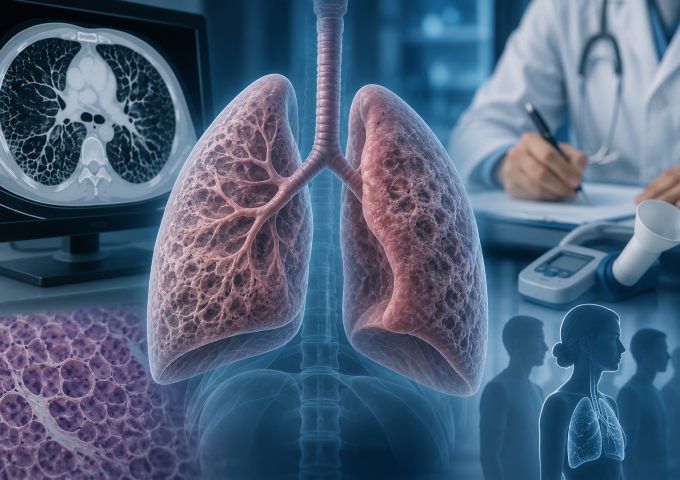

Наразі існуючі методи оцінки пасивного крутного моменту суглобів обмежуються лабораторними умовами, що утруднює застосування їх у клінічній практиці. Одним з перспективних інструментів є ультразвукова еластографія зсувної хвилі, яка дозволяє об’єктивно оцінювати механічні властивості м’язів, такі як їх пружність і жорсткість, що безпосередньо впливає на опір при рухах суглобів.

Ультразвукова еластографія вже довела свою ефективність у клінічних умовах при оцінці стану м’язів у пацієнтів з геміпарезом, спричиненим інсультом. Метод дозволяє отримати точні дані про м’язову жорсткість та механічні властивості суглобів, що можуть бути використані для покращення діагностики та корекції реабілітаційних підходів.

Дослідження, проведене в рамках нещодавнього наукового проєкту, показало, що швидкість зсувної хвилі в м’язах, зокрема двоголового м’яза плеча, корелює з пасивним крутним моментом суглоба, що може стати основою для об’єктивної оцінки механічних змін в тканинах. Зокрема, у пацієнтів з паретичними кінцівками спостерігається значно вищий крутний момент і швидкість зсувної хвилі порівняно з непаретичними кінцівками.

Для цього дослідження було використано 12 осіб, які перенесли хронічний інсульт. Учасники проходили обстеження за допомогою електроміографії (ЕМГ) та ультразвукової еластографії зсувної хвилі для визначення механічних властивостей м’язів у різних положеннях ліктьового суглоба. Отримані дані свідчать про важливість врахування кута суглоба при аналізі механічних характеристик м’язів та суглобів.

Для клінічної практики це відкриває нові можливості для об’єктивної оцінки фізіологічних змін у пацієнтів після інсульту, що дозволить більш точно вибирати методи реабілітації та корекції рухових функцій.

Таким чином, ультразвукова еластографія зсувної хвилі є перспективним методом для покращення оцінки стану пацієнтів та розробки нових реабілітаційних стратегій, спрямованих на відновлення рухових функцій після інсульту.